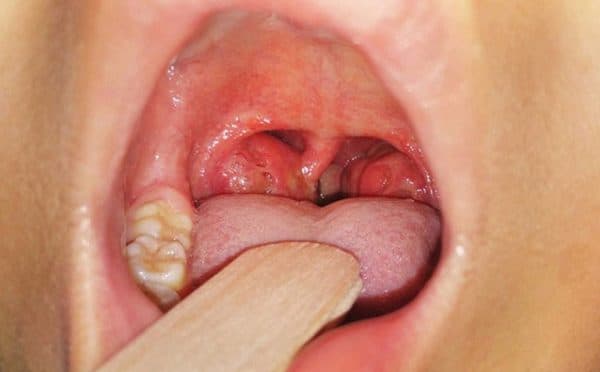

Viêm amidan mạn tính: Đây là tình trạng nhiễm trùng amidan dai dẳng hoặc là kết quả của việc amidan cấp tính tái phát nhiều lần. Viêm amidan khi phát triển to lên thường gọi là viêm quá phát, hoặc nếu nhỏ lại được gọi là viêm xơ teo, tình trạng nhiễm trùng ở cả 2 khối amidan thì gọi là viêm amidan hốc bã đậu.

– Viêm amidan hốc bã đậu bị bao phủ bởi lớp mủ trắng vón lại thành kén. Bệnh nhân có thể khạc ra mủ màu như bã đậu trắng, hơi thở có mùi, hôi miệng.

– Viêm amidan quá phát hay còn được biết đến với tên gọi viêm amidan phì đại, ở trường hợp này ổ viêm thường lớn bất thường và được chia thành 3 cấp tương đương với kích thước amidan

– Viêm amidan xơ teo là dạng phổ biến nhất đối với người lớn. Với dạng này thì bề mặt amidan sẽ trở nên gồ ghề, viêm tái đi tái lại nhiều lần. Khi ấn tay vào amidan thì ở các hốc sẽ tiết ra mủ rất hôi